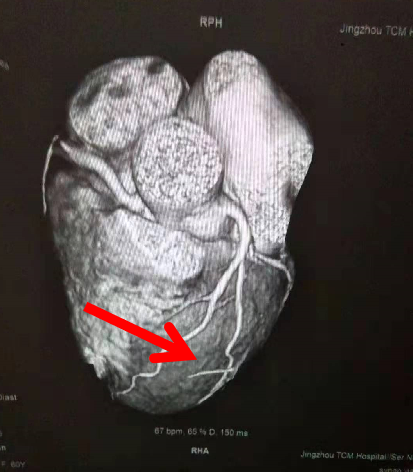

【病 史】患者诉每日夜间憋醒患者心前区间断疼痛数年,未规范诊治。一天前心前区疼痛症状加重并放射至背部疼痛,就诊于荆州市中医医院。入院检查CT示:冠状动脉粥样硬化,左前降支阻塞80%~90%,心肌缺血。医生根据结果要求患者做支架治疗,患者拒绝后出院,于15年12月15日来我社区卫生院门诊就诊。根据患者情况,医生给予TTS治疗。

TTS治疗结果:当日开始用新汉方TTS为患者进行治疗,三天后患者自诉体感症状消失;随后共进行23次治疗,症状消失,一般情况均好;患者再去荆州市荆州市中医医院复查,报告其心脏左前降支阻塞60%~70%。